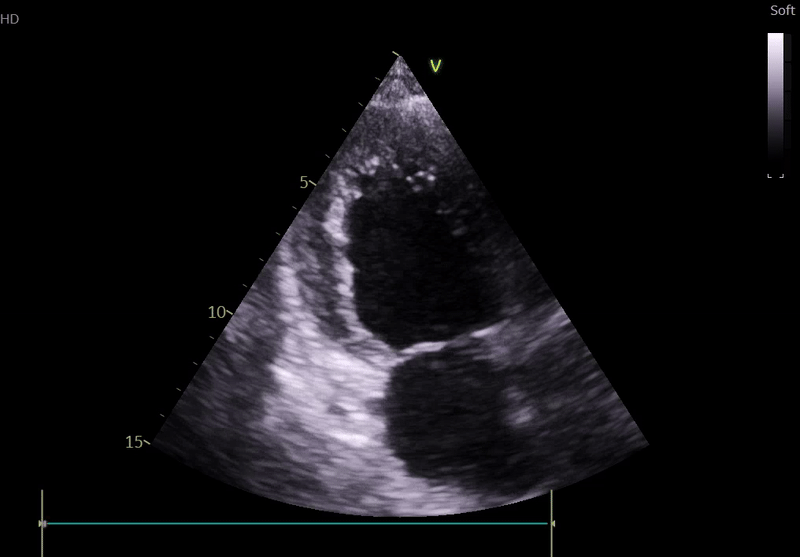

Echocardiography on admission:

Transthoracic Echocardiography on Admission

• Mildly dilated left ventricle (LVEDD 55 mm)

• Severe global hypokinesis

• Left ventricular ejection fraction 20–25%

• Mild mitral regurgitation

• Right ventricle normal in size and systolic function